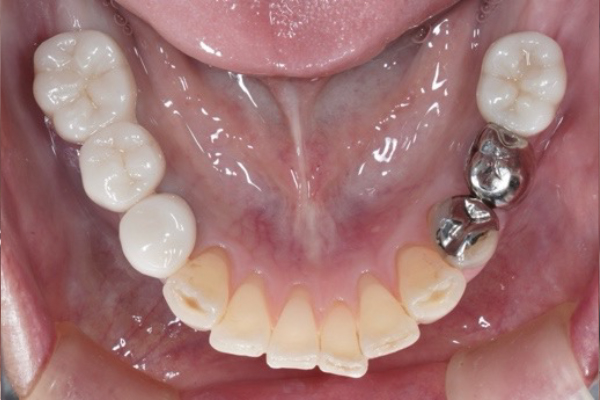

AFTER

①左下大臼歯部骨造成

②骨造成後6ヶ月待ちます

③インプラント埋入と同時にもう一度骨造成

④歯肉移植

⑤最終補綴セット

抜歯してから長期に渡り入れ歯を使用していたので骨が非常に薄くなってしまっていました。インプラント治療を長期的に成功させるためには骨の状態は大変重要です。

骨造成、歯肉移植は術後に腫れ、内出血、痛みを伴うことが多いです。

患者様は複数回の手術に耐えて大変頑張っていただけました。これからはメインテナンスのフェーズに入ります。定期的なクリーニングと咬合チェックを怠らないことで、インプラント周囲炎の発症リスクを大幅に抑えられます。

長期に渡りインプラントを使用できるようしっかりと経過を追わせて頂きます。